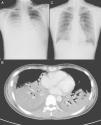

A) Radiografía de tórax, que mostraba infiltrados alveolares en ambos campos pulmonares. B) Tomografía computarizada de tórax, que mostraba consolidaciones difusas con broncograma aéreo en ambos lóbulos inferiores, una consolidación subsegmentaria en el segmento medial del lóbulo medio derecho y un derrame pleural mínimo. C) Tras el tratamiento con ribavirina inhalada, la radiografía de tórax puso de manifiesto una resolución evidente de la consolidación en los lóbulos inferiores de ambos pulmones.

Caso clínicoUna mujer de 32 años, universitaria, previamente sana, fue ingresada en la unidad de cuidados intensivos (UCI) del Taipei Veterans General Hospital procedente de un hospital local, en el que había sido ingresada a causa de un cuadro de 4 días de fiebre alta, tos con escasa producción de esputo y disnea. La paciente no había sido nunca fumadora, no seguía tratamiento médico alguno y sus antecedentes clínicos previos no mostraban ninguna enfermedad relevante. Al ingreso, la exploración física puso de manifiesto la presencia de estertores respiratorios en ambos campos pulmonares, pero no había ingurgitación venosa yugular ni signos anormales a la auscultación cardiaca. Los análisis de laboratorio mostraron un recuento leucocitario de 5.500/mm3, con un 92% de neutrófilos, un 0% de bandas y un 4% de linfocitos. La tinción de Gram del esputo mostró pocos neutrófilos polimorfonucleares, células epiteliales muy poco frecuentes y ningún patógeno bacteriano o fúngico. A su llegada a nuestro hospital, la paciente presentaba una gasometría con máscara de oxígeno sin reinhalación (O2: 15 l/min) con pH=7,49, PaO2=70mmHg, PCO2=33,5mmHg, HCO3−=20 mmol/l y saturación de O2=95,7%. La radiografía de tórax (RxT) inicial obtenida en nuestro hospital mostró infiltrados alveolares difusos en ambos campos pulmonares (fig. 1A) Todos los síntomas y signos cumplían los criterios del SDRA.

Se realizó una intubación endotraqueal con apoyo de ventilación mecánica 4 horas después del ingreso, debido al deterioro muy rápido del estado respiratorio. Tras la intubación, fue necesaria una concentración de oxígeno inspirado del 100%, con presión teleespiratoria positiva de 12cm H2O, y un volumen corriente de 400ml para una oxigenación adecuada. La TC torácica mostró la presencia de consolidaciones difusas con broncograma aéreo en ambos lóbulos inferiores, y una consolidación subsegmentaria en el segmento medial del lóbulo medio derecho (fig. 1B). La broncoscopia de fibra óptica puso de manifiesto una pequeña cantidad de secreción de las vías respiratorias en los bronquios de ambos lados, pero por lo demás no mostró alteraciones. Las tinciones para bacterias, hongos y tuberculosis, así como los cultivos de esputo y de líquido de lavado broncoalveolar (LLBA) dieron todos resultados negativos. El ensayo inmunosorbente ligado a enzimas para IgM específica para el citomegalovirus y el virus del herpes simple, los anticuerpos y el antígeno urinario de la legionelosis, la prueba de látex para el antígeno criptocócico sérico, la técnica de anticuerpos inmunfluorescentes para la IgM específica para la cápside del virus de Epstein-Barr y la IgM para clamidias, y la prueba de aglutinación de partículas para el anticuerpo para Mycoplasma pneumoniae (M. pneumoniae) fueron negativos. El inmunoensayo enzimático (EIA) para anti-VIH en suero fue también negativo. La tinción O de azul de toluidina y la prueba de reacción en cadena de polimerasa para citomegalovirus (CMV-PCR) en el LLBA fueron negativos, pero la prueba de EIA para el antígeno de VRS en el LLBA fue intensamente positiva. Inicialmente, antes del diagnóstico de la infección por VRS, esta paciente había sido tratada con la administración intravenosa de levofloxacino, imipenem, teicoplanina y metilprednisolona, pero no se observó mejoría alguna en los síntomas o signos clínicos ni en la infiltración pulmonar existente en la RxT 7 días después del ingreso. Se administró, pues, ribavirina inhalada (Virazole; Ben Venue Laboratory, Inc; Bedford, OH) (6g en 300ml de suero fisiológico normal, de forma continuada durante 18 horas al día) durante tres días, empezando al octavo día de ingreso. La RxT de seguimiento mostró una reducción evidente de la consolidación en ambos campos pulmonares (fig. 1C) y hubo una notable mejoría de todos los signos y síntomas clínicos. Dado el SDRA grave, se tardó más tiempo en extubar a la paciente. Finalmente, fue extubada de forma satisfactoria a los 14 días de hospitalización y fue dada de alta a los 22 días del ingreso para un seguimiento ambulatorio, sin oxigenoterapia. La gasometría arterial respirando aire ambiental, en el momento del alta era de pH=7,44, PaO2=97mmHg, PCO2=40mmHg, HCO3−=27 mmol/l, y saturación de O2=98%. Las pruebas de la función pulmonar antes y 4 meses después del alta fueron de FVC: 79%, DLCO: 55%, DLCO/volumen alveolar: 3,35 (66%) y FVC: 104%, DLCO: 72%, DLCO/volumen alveolar: 3,93 (77%), respectivamente. No hubo sibilancias ni tos seca tras el alta. El recuento de células T CD4+ fue inicialmente de 198/mm3 al ingreso, y luego se recuperó hasta alcanzar un valor de 554/mm3 dos meses después del alta.